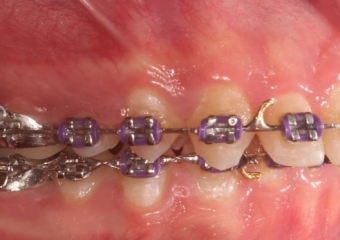

Mordida inicial

Mordida após a cirurgia